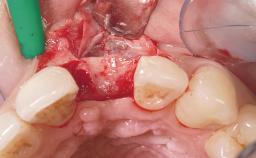

Immediate Flapless Placement of an Implant in a Maxillary Left Central Incisor Site

A 42-year-old female patient was referred to our clinic at the School of Dentistry of the University of São Paulo in November 2004, presenting a deficient restoration in the upper left central incisor. The clinical examination revealed no gingival retraction or any signs of gingival inflammation and, therefore, previous periodontal treatment was not considered. The patient presented a high lip line at full smile and a thin tissue biotype. This combination characterized a high-risk situation from an anatomic point of view, which required careful preoperative planning and cautious surgical execution.

Placement Protocol Immediate implant placement

Bone Volume Sufficient, with intact walls

Esthetic Risk Medium